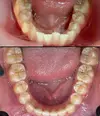

Crooked Teeth